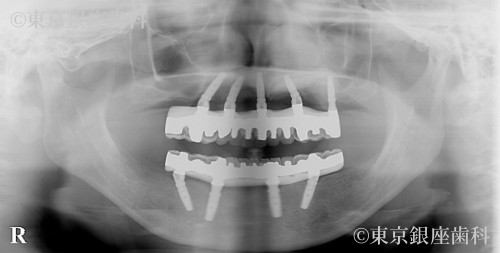

歯周病の進行により歯に動揺があり長期の保存が難しく、臼歯の欠損で咬み合わせが下がって前歯部への負担が大きくなっているため全顎的な治療が必要と判断し上下顎でワンデイインプラントを行うことにした。

重度の歯周病によりOPE時の出血量が多かったためOPEを二回に分けた(上顎、下顎)。

また上顎骨が薄く左側は上顎洞に骨を足す治療(サイナスリフト)を行い上顎に5本のインプラントを埋入。

当日下顎は抜歯のみを行い、炎症が収まるまで義歯待機。上顎OPEから2か月後下顎4本埋入。仮歯を入れ噛み合わせを安定させた為、顎の変位も改善された。